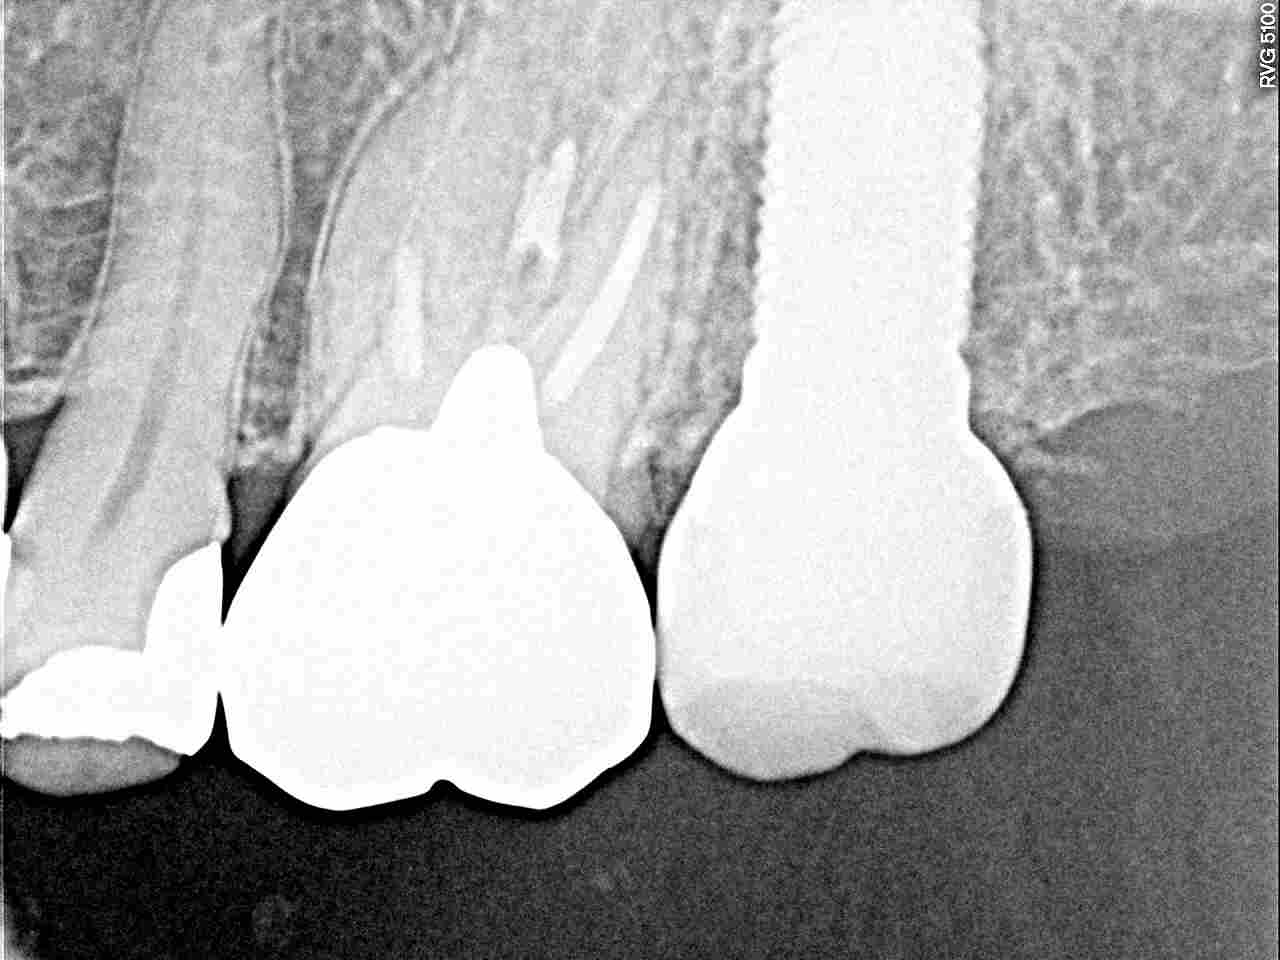

左上7番のインプラントの上部構造を入れていきます|お知らせ |広島市安佐南区の歯科医院 左上7番のインプラントの上部構造を入れていきます トップ お知らせ・ブログ お知らせ 左上7番のインプラントの上部構造を入れていきます 左上7番のインプラントの上部構造を入れていきます 埋入直後になります 縫合して終了しています 2か月後に頭出しを行いさらに10日がたっています 傷が治ってきました このように2か月半ではきれいにいっています チタンのカスタムのアバットメントを作成しています 5mmの13mmというインプラントを埋入しています 上部構造をこのようにきれいに仕上がっています かなりしっかりしたインプラントが入りました Web診療予約 初めての方へ 選ばれ続ける理由 院内設備について 歯が痛いしみる一般歯科 歯がぐらぐらする歯周病 健康な歯を保ちたい予防歯科 子供の虫歯予防をしたい小児歯科 銀歯をセラミックに審美歯科 白い歯を目指しませんか?ホワイトニング 矯正専門医がいるので安心矯正歯科 抜けた歯を補いたいインプラント・入れ歯 医院案内 スタッフ紹介 メリィハウス歯科クリニックオフィシャルホームページ ラベンダー歯科クリニックオフィシャルホームページ お知らせ・ブログ ホーム 診療科目 一般歯科 歯周病治療 予防治療 小児歯科 審美治療 ホワイトニング 矯正歯科 入れ歯・インプラント マウスピース矯正 初めての方へ 院長・スタッフ 設備紹介 医院案内・アクセス メニューを閉じる